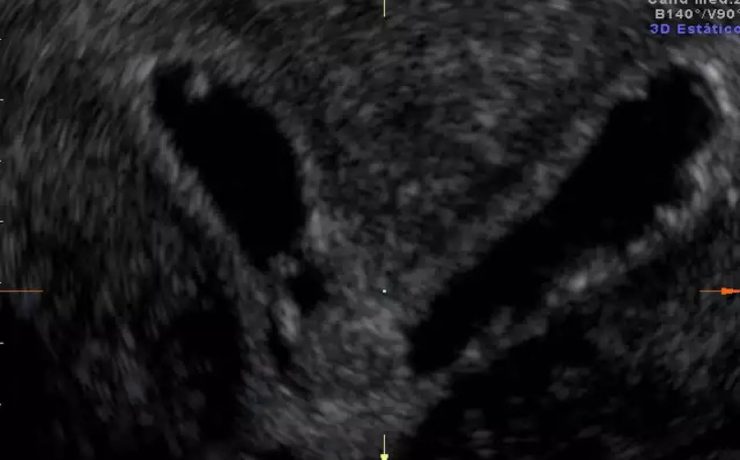

Patologías benignas de la próstata: prostatitis e hiperplasia benigna

En este estudio se llevó a cabo un análisis de la anatomía prostática; los factores más relevantes que regulan el crecimiento prostático y y las funciones de la glándula que podrían influir en la etiología de diferentes patologías de la próstata; parámetros claves en el diagnóstico temprano y de estas